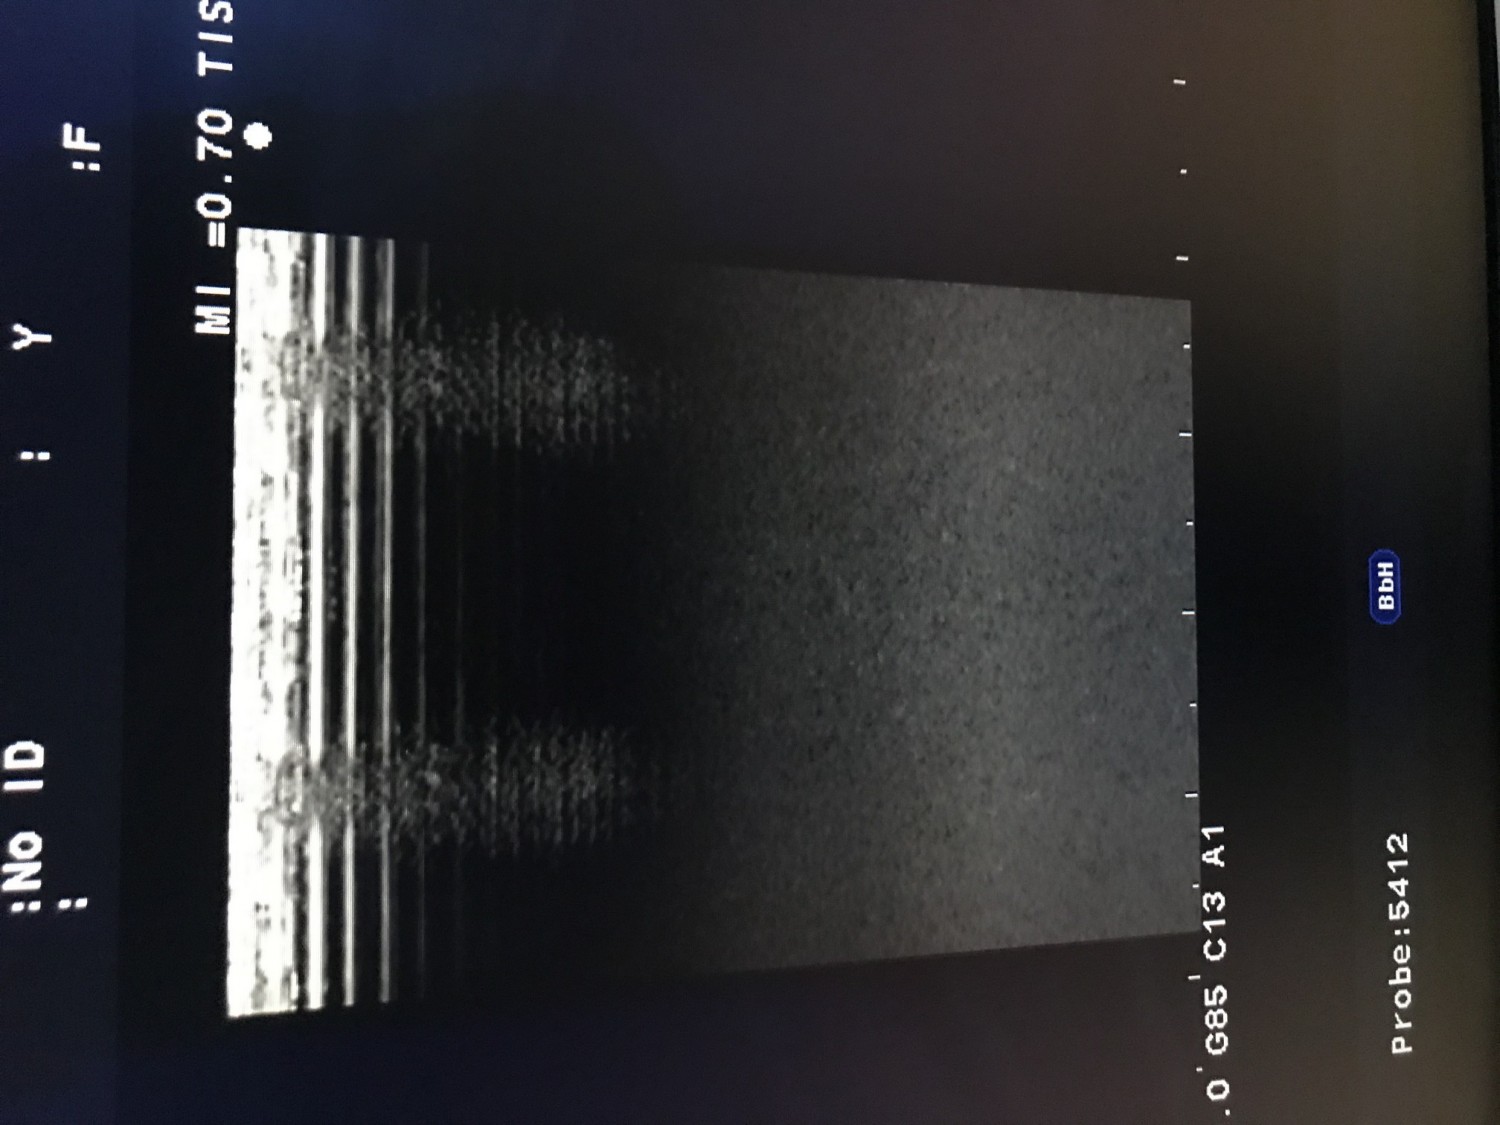

Подскажите кто сталкивался с данным аппаратом где добыть сервисный мануал. Какой блок может давать такую картинку?

6259734.jpg (104.5 Kb)

Сообщение отредактировал vik_rock - Понедельник, 13.Июл.2015, 14:56

Сервис мануал не поможет, там про это ничего нет. Проблема такая изредка бывает на Альфах 6. Должно проявляться на всех датчиках, но не факт что на всех портах.

Обычно это плата либо DBF (digital beam former), либо Beam Processor.

Вот ещё пример аналогичный:

Меняются обычно обе платы (если по гарантии), т.к. вычислить конкретный блок крайне сложно. Но лучше начать с DBF.

Скиньте серийный номер, я просчитаю стоимость этих запчастей. Как вариант можно в сервисном меню включить maintanance tool и там по-переключать платы и посмотреть, что будет происходить, хотя это не факт что выявит точную плату.

DBF у нас припасена если что. Можем выслать на тест, но тогда договор надо заключить.